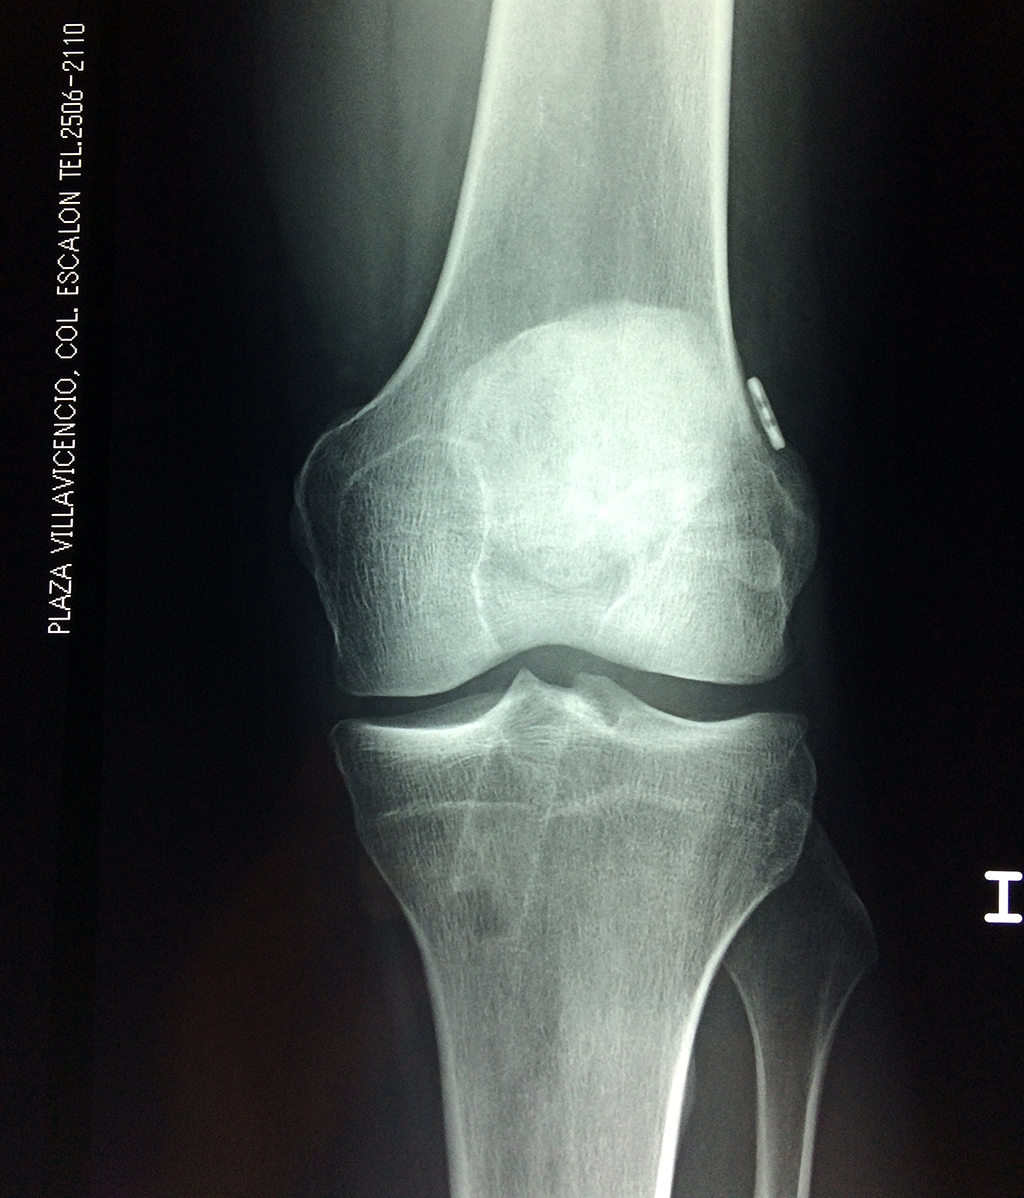

Cirugías de Calcaneo - Rodilla